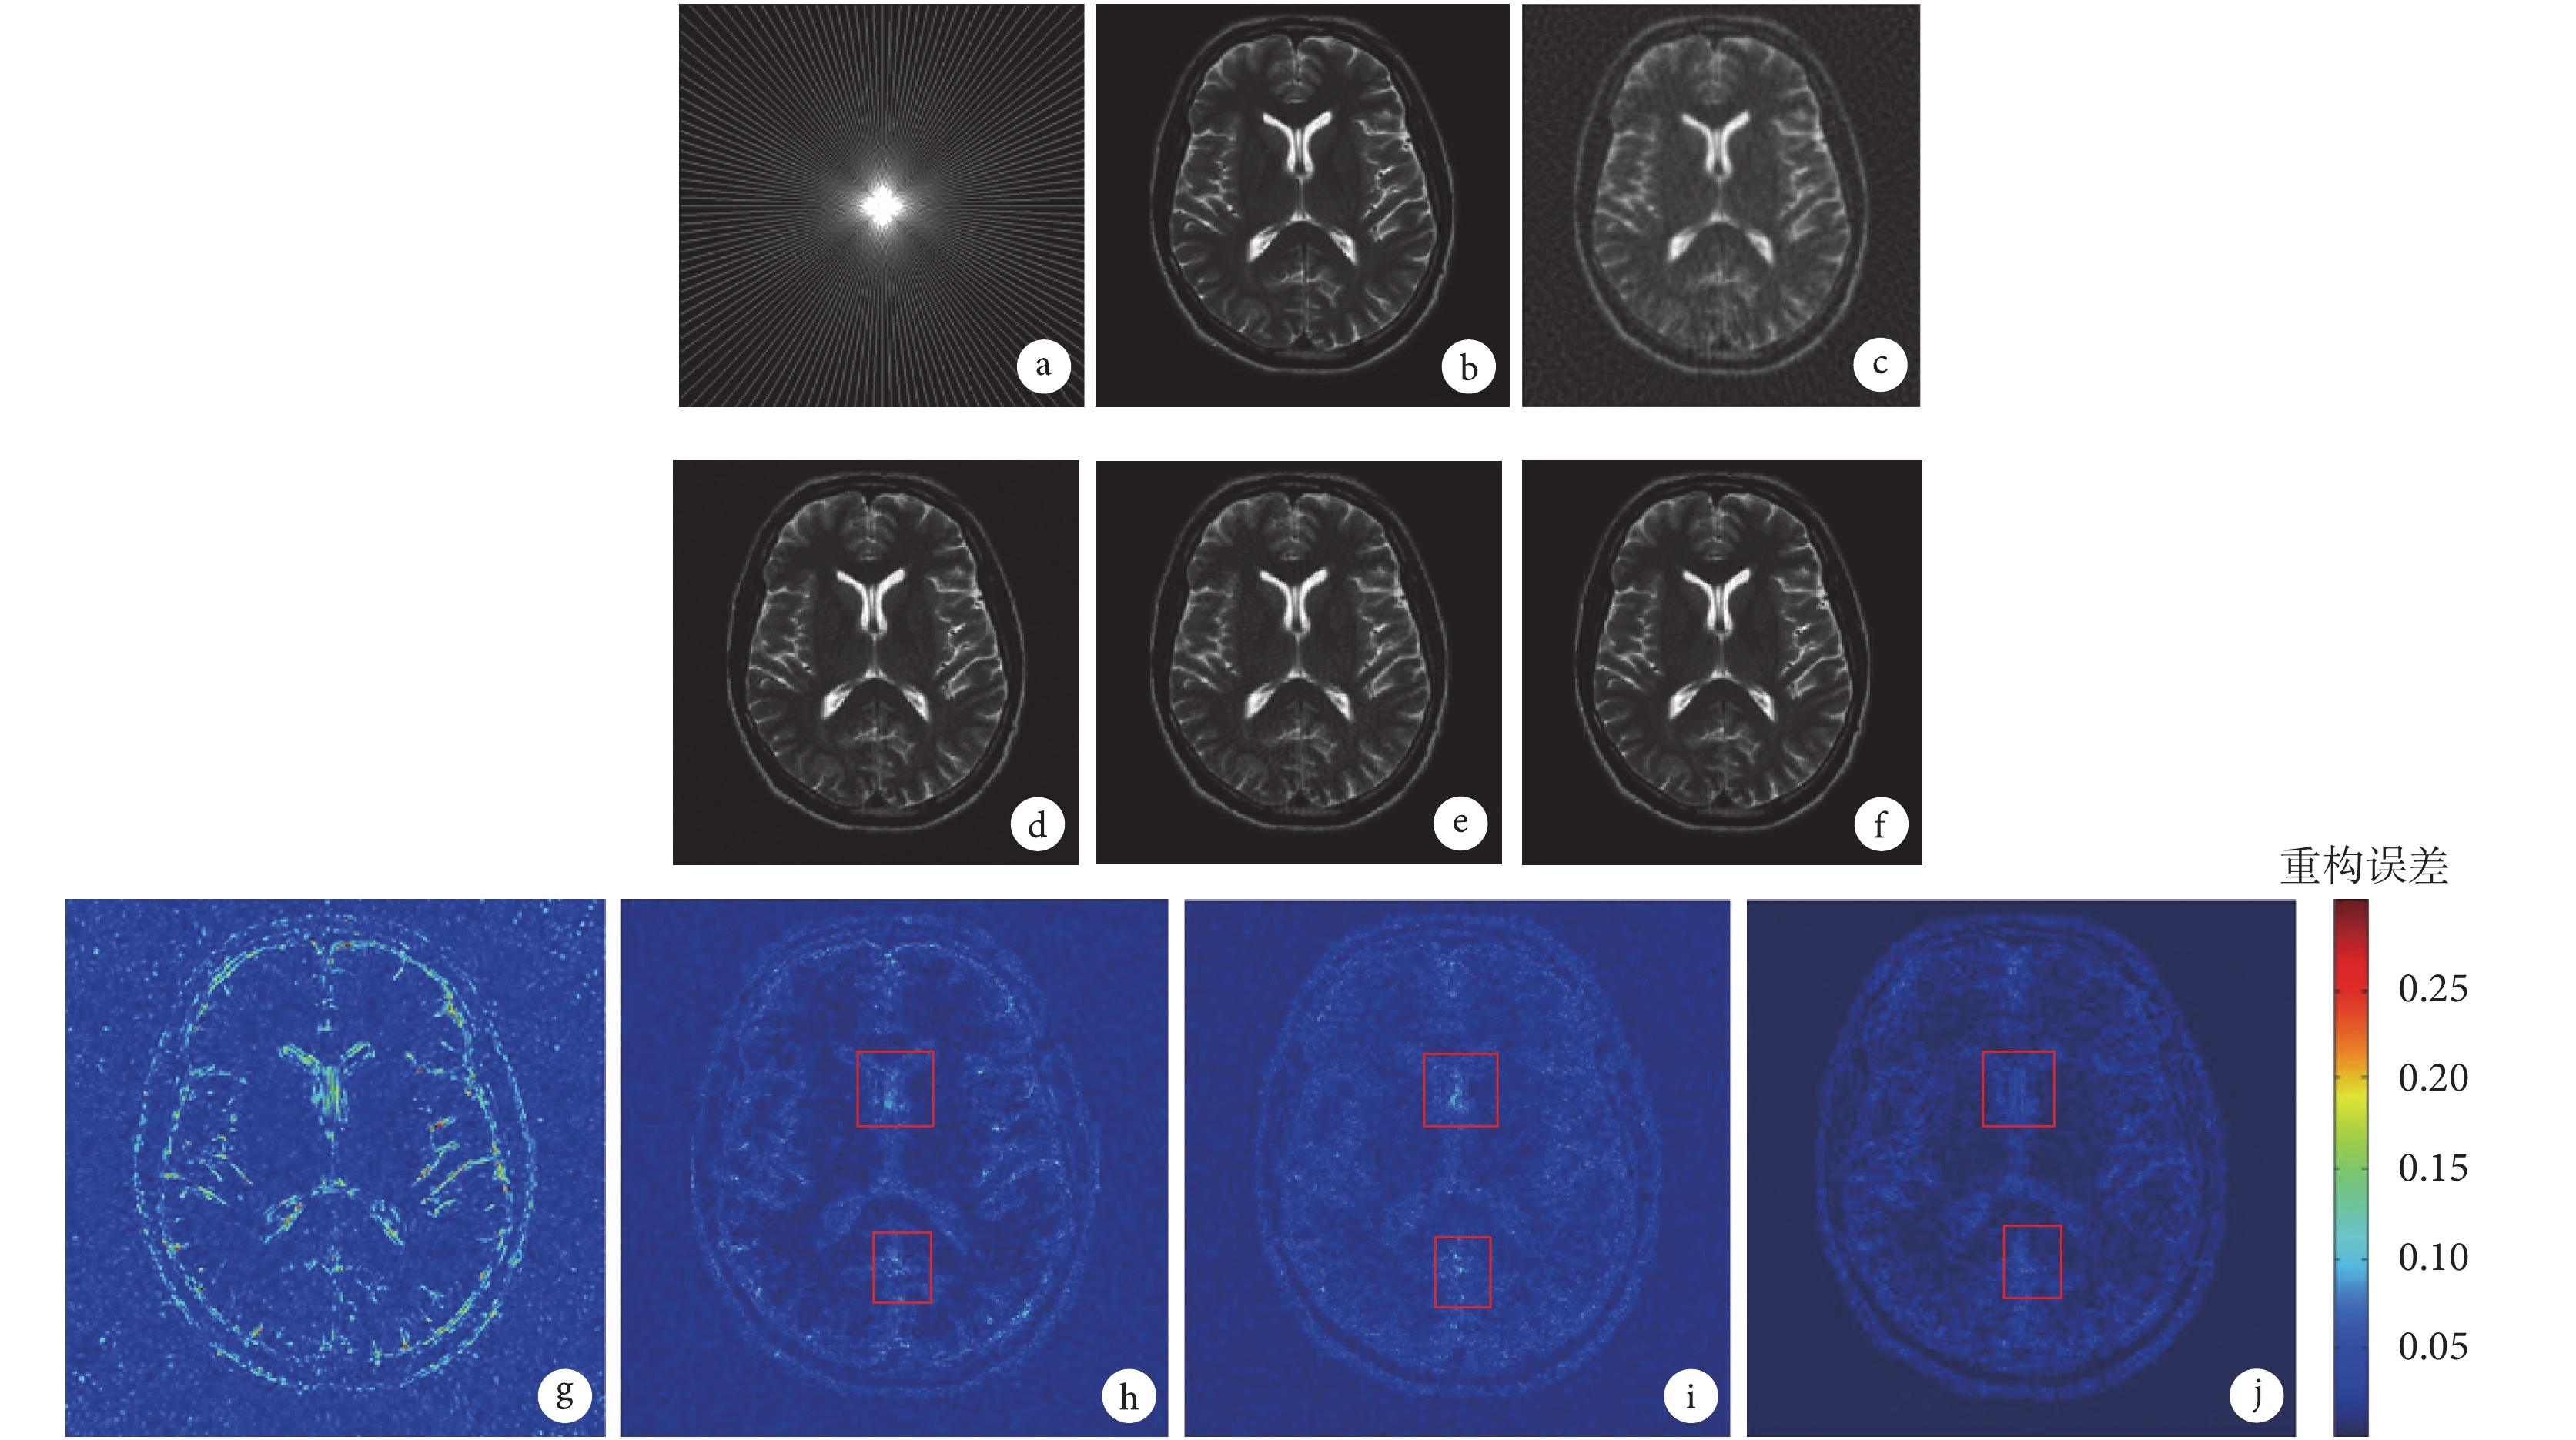

為了進一步體現本文提出模型的優越性,將從主觀視覺效果方面評價 MR 圖像的重構效果。圖 3 給出了 2D 變密度隨機采樣 R = 10%、σ = 35 時,各重構模型對 Brain 圖像局部(所取部分在圖 1b 中已標出)重構結果的比較圖;圖 4 給出了偽射線采樣 l = 80、σ = 35 時,各重構模型對 t2axialbrain 圖像的重構結果和重構誤差圖。由圖 4h、4i、4j 可見,相比 TLMRI 和 DLMRI 模型,DTKMRI 模型圖像重構質量在紅色矩形區域得到明顯改善。圖 3 和圖 4 給出的重構結果中,Zero-filling 的 MR 圖像重構質量最差,細節信息丟失最多,平滑和邊緣部分模糊;DLMRI 的 MR 圖像重構質量明顯優于 Zero-filling,但仍丟失了大量細節信息,圖像過于平滑,邊緣輪廓結構不清晰;TLMRI 的 MR 圖像重構質量優于 DLMRI,邊緣輪廓結構較之更為清晰,但仍丟失了部分細節信息;DTKMRI 的 MR 圖像重構結果中保留了更多的細節信息,邊緣輪廓結構較清晰,重構結果中噪聲不明顯。可見,DTKMRI 能夠更精確地重構 MR 圖像的細節信息和邊緣輪廓結構信息。

a. K-空間的偽射線采樣;b. 原圖像;c & g. Zero-filling;d & h. DLMRI;e & i. TLMRI;f & j. DTKMRI。圖 h、i、j 的紅色矩形區域表示:相比 DLMRI 和 TLMRI,DTKMRI 的圖像重構質量得到明顯改善

Figure4. The t2axialbrain image reconstruction results and errors of different models under pseudo radial samplinga. pseudo radial sampling in the K-space; b. original image; c & g. Zero-filling; d & h. DLMRI; e & i. TLMRI; f & j. DTKMRI. Compared to DLMRI and TLMRI, DTKMRI remarkably improves the reconstruction quality of the image in the red rectangle boxes of Fig.4 h, i, j